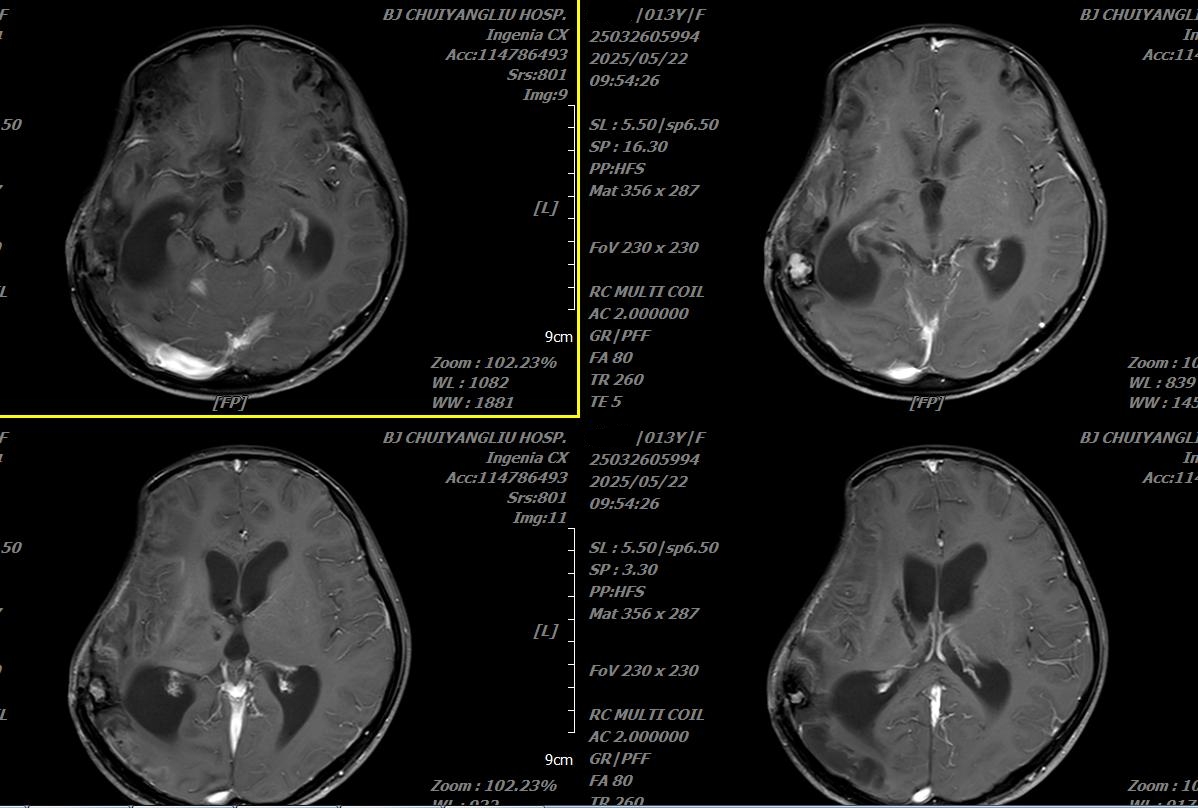

出院前头颅增强MRI

2025年5月23日,历时58天,小雨终于顺利出院了,再看小雨,体温早已正常,并且可以自主进食、排尿、在爸爸的搀扶下行走,并且可以大声地喊出“我回家了!”